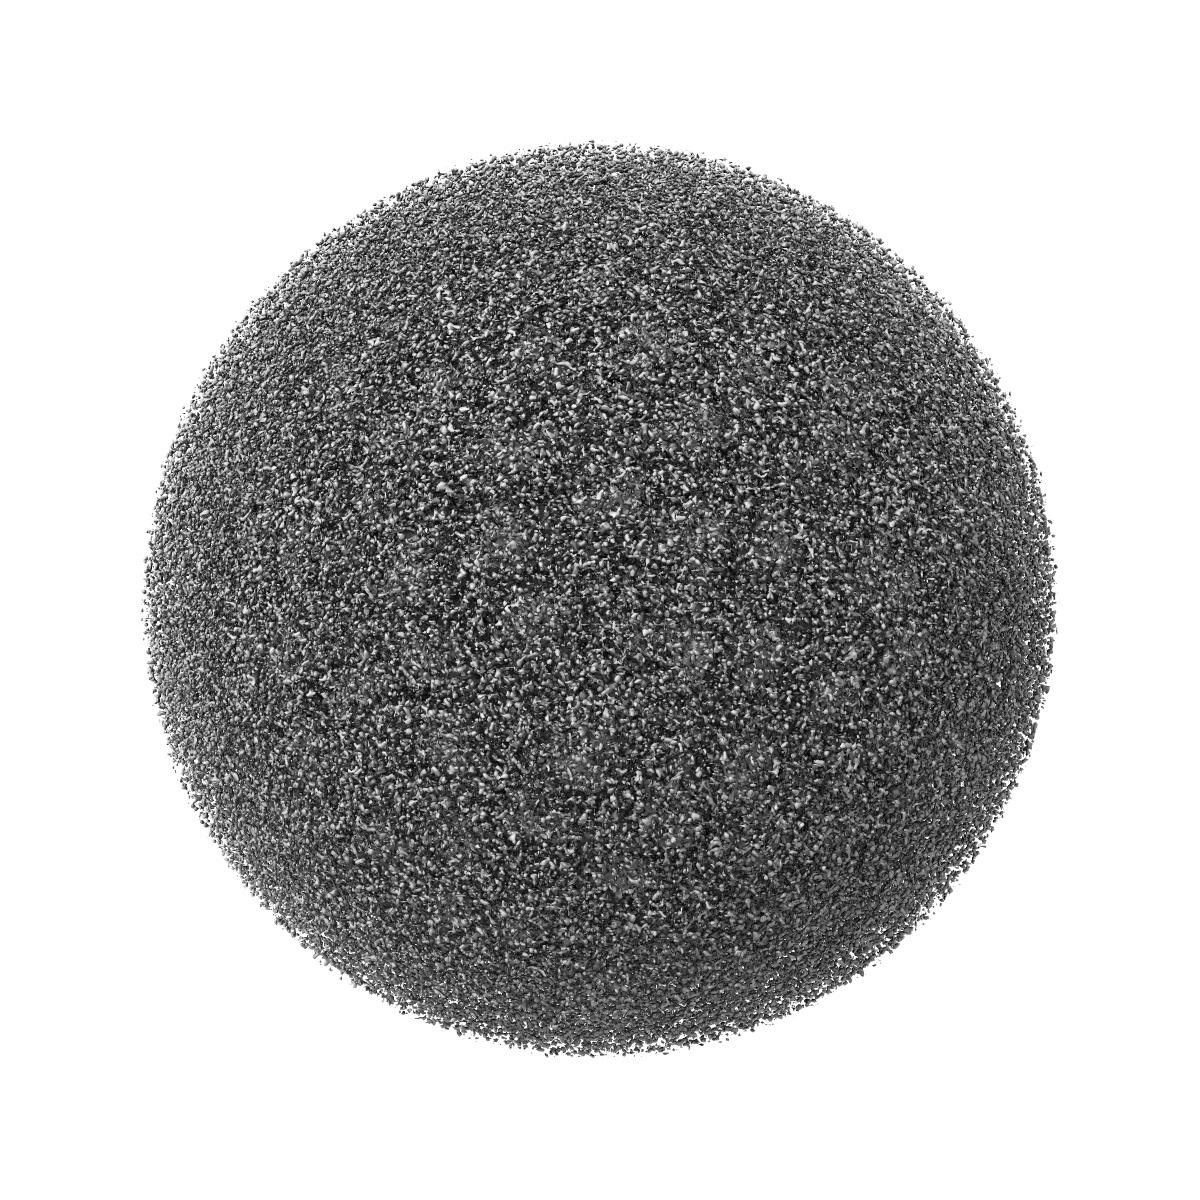

Cryo-EM structure of Dengue virus serotype 2 in complex with antigen-binding fragments of human antibody 2D22

Single-particle6.5 Å

Sample: Dengue virus serotype 2 strain PVP94/07 (a clinical isolate) complexed with Fab fragments of human antibody 2D22.

DENGUE VIRUS. Cryo-EM structure of an antibody that neutralizes dengue virus type 2 by locking E protein dimers.